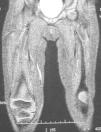

La resonancia magnética (RM) muestra atrofia generalizada de los músculos del compartimento anteroexterno y degeneración lipofibromatosa del vasto intermedio que afecta a todo su trayecto asociándose a una banda fibrosa gruesa que se fusiona con el tendón cuadricipital. Secundariamente, por retracción, apreciamos una posición alta de la rótula con desplazamiento hacia fuera (figs. 2 y 3).

Figura 2. RM de extremidades inferiores, secuencia ponderada en T1, proyección axial, que muestra atrofia generalizada de los músculos del compartimento anteroexterno y degeneración lipofibromatosa del vasto intermedio izquierdo.